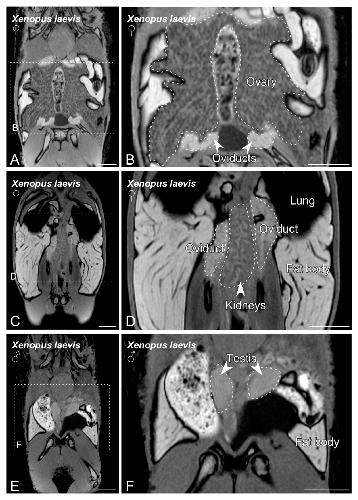

Figure 3. MRI slices selected to illustrate the main sex organs of the Xenopus laevis anurans. Images from (A) to (D) show the structures identified in a gravid Xenopus laevis female. Images (E,F) show testis and fat body in a Xenopus laevis male. The dashed lines in (A,C,E) indicate the magnification photos showed in (B,D,F). Scale bars = 1 cm. |